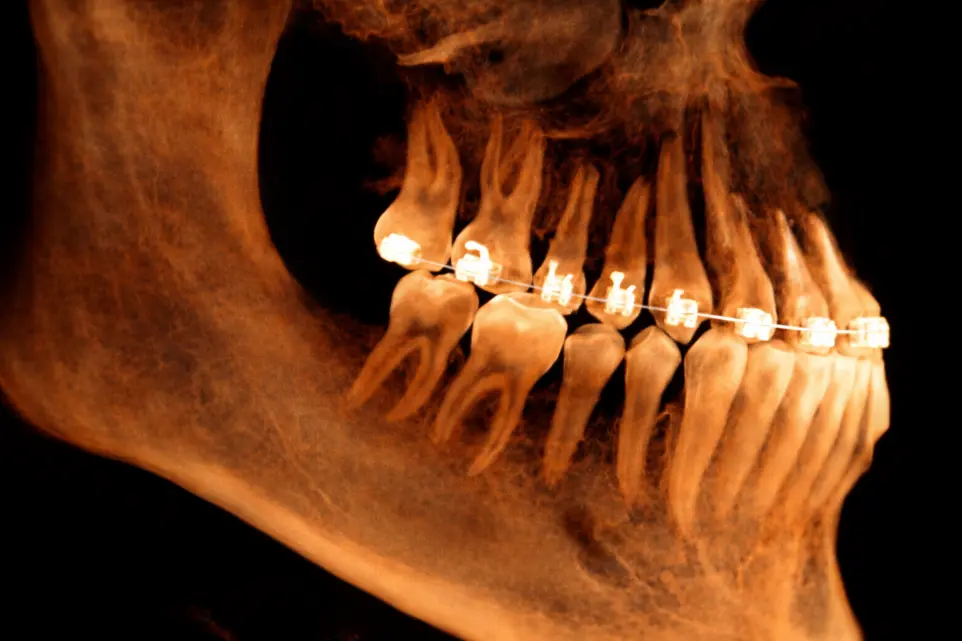

TOMOGRAFÍA DE IMPLANTES

Cuando es necesario evaluar las condiciones óseas de los rebordes alveolares.